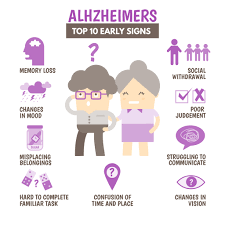

نشانه های اولیه آلزایمر: 10 علامتی که نباید نادیده بگیرید